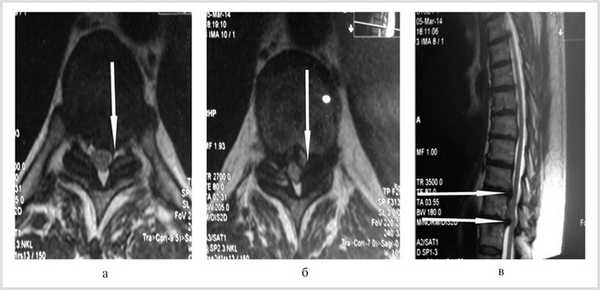

Больной обследован. При спондилографии грудного отдела позвоночника выявлен остеохондроз Th III —Th IV , II период, Th VIII —Th XII III период; данные MPT грудного отдела позвоночника: грыжи межпозвонковых дисков Th III —Th IV , Th IX —Th X , Th X —Th XI (рис. 1). При электронейромиографии нижних конечностей обнаружены выраженные изменения по аксональному типу в левом и правом малоберцовом нервах.

Рис. 1. Магнитно-резонансные томограммы грудного отдела позвоночника (Т1 режим): в аксиальной (а, б) и сагиттальной (в) плоскостях до операции.

Неврологический статус при поступлении: положение в постели лежа, анталгическое. Самостоятельно не передвигается вследствие нижнего спастического парапареза. Перкуссия остистых отростков грудного отдела позвоночника резко болезненна с уровня Th VII до верхнепоясничного отдела позвоночника. Коленные рефлексы справа и слева высокие, ахилловы справа и слева высокие. Вальгусная деформация обеих стоп. Клонус нижних конечностей. Симптом Бабинского положительный с обеих сторон. Рефлекс Бехтерева—Менделя положительный с обеих сторон. Мышечный тонус в руках нормальный, в ногах повышен по центральному типу. Сила в руках 5 баллов, в ногах снижена до 2 баллов с обеих сторон. Нарушения чувствительности в виде гипестезии от дерматома D и ниже. Тазовые нарушения по типу парадоксальной ишурии. Уровень болевого синдрома по визуальной аналоговой шкале 92 балла, по шкале Nurick 4 балла [1].

Локально: трофические нарушения (пролежни) в пяточной области с обеих сторон. Диагноз: остеохондроз грудного отдела позвоночника. Грыжи межпозвонковых дисков Th IX —Th X , Th X —Th XI со стенозированием позвоночного канала и сдавлением спинного мозга. Компрессионная миелопатия. Нижний спастический парапарез. Тазовые расстройства по типу парадоксальной ишурии. Трофические нарушения в виде пролежней в пяточных областях с обеих сторон.